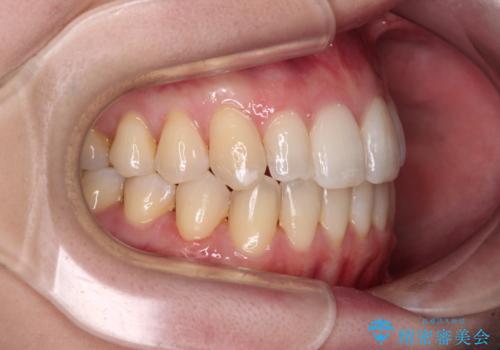

補助装置を併用したインビザラインでの八重歯の抜歯矯正

- 八重歯と奥歯の咬み合わせを気にして来院された患者様です。

インビザラインによる矯正治療を希望されたため、八重歯改善のための抜歯矯正部分は補助装置を併用し、その後はインビザラインにて行うこととしました。

下顎の右側変位が顕著であったため、ワイヤー矯正の方が咬み合わせは改善しやすいのですが、ある程度は時間がかかっても良いとのことであったので、インビザラインにて矯正治療を行うこととしました。

骨格的に下顎が右側に変位していたため、上下正中を合わせることは困難であることは分かっていました。それでも、なるべく合わせるようにとしたため、治療期間は長期間となりました。

長期間とはなりましたが、咬み合わせが改善され、患者様には大変満足していただきました。